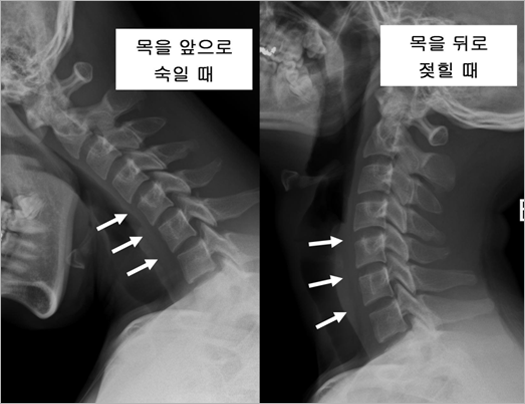

| 추간판은 주로 척추를 따라 전달되는 하중과 충격을 완화시켜주는 쿠션 역할을 하기도 하며, 척추체사이에 약간의 움직임을 허용할 수 있는 여유 공간으로서 작용하기도 합니다. 그림 2는 정상인에서 목을 앞으로 숙일 때와 뒤로 젖힐 때 각각 촬영한 엑스레이 사진입니다. |

| • 그림 2 정상인의 경추 엑스레이 |

| 하얗게 보이는 부분이 척추체이고, 그 사이에 까맣게 비어있는 것처럼 보이는 공간(화살표)이 바로 추간판입니다. 추간판은 말랑말랑한 조직이기 때문에 엑스레이에서는 보이지 않습니다. 언뜻 봐서는 차이를 잘 모르겠지만 목을 앞으로 숙일 때는 척추체 앞부분의 간격이 좁아지고 뒤로 젖힐 때는 넓어지는 것을 관찰할 수 있습니다. 이것은 목의 운동에 따라 추간판의 모양이 변화한다는 것을 의미하며, 거꾸로 말하면 추간판이 변형될 수 있어야 목(경추)의 움직임이 가능하다고 할 수 있습니다. 정상 성인에서는 각 추간판 마디마다 약 10도 정도의 움직임이 가능하다고 알려져 있는데 이것은 추간판이 정상적인 기능을 유지하고 있을 때에만 가능합니다. 추간판은 비록 작지만 구조나 기능, 생리학적인 면에서 매우 복잡한 구조물이어서 현재까지 수많은 의학자와 과학자들이 연구를 계속하고 있으나 아직까지도 그 비밀이 완전히 밝혀지고 있지 않습니다. 다만 최근 목의 운동 중에 생기는 추간판의 변형을 모방해서, 움직임이 가능한 원판 모양의 기계 장치를 개발해 내었는데 이것이 인공디스크이며, 이 중 경추 추간판에 맞게 만든 것이 경추 인공디스크입니다. 경추 인공디스크는 한 가지 형태만 있는 것이 아닙니다. 주로 유럽과 미국에서 수많은 모델의 제품이 개발되었는데, 어느 정도 안정성이 입증되어 우리나라에서 실제 사용되고 있는 것은 약 10여종에 달합니다(그림 3). 하지만 어떠한 모델이건 기본적인 구조는 거의 동일하다고 할 수 있습니다. 우선 추간판이 제거되고 노출된, 위 아래 척추체의 단면과 접촉하여 단단히 유합될 수 있는 두 개의 판이 있고, 그 사이에 움직임을 만들어 줄 수 있는 "베어링" 구조가 끼어 있습니다. 그림 3을 보시면 쉽게 이해할 수 있을 것입니다. |